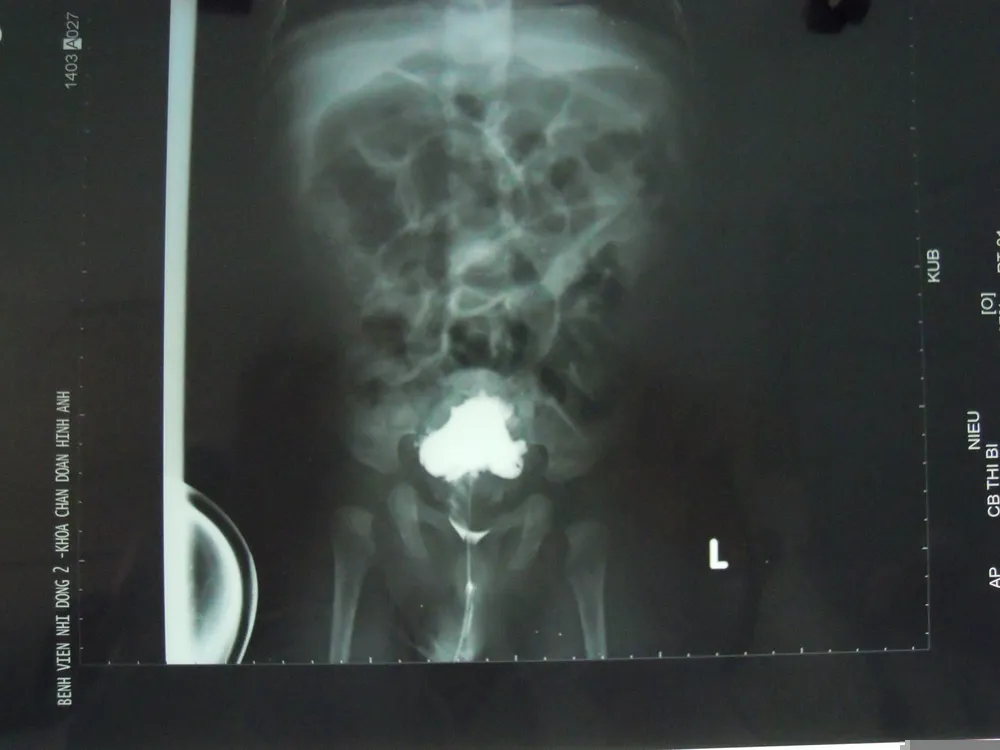

Hình ảnh Cận lâm sàng thành bàng quang nham nhở